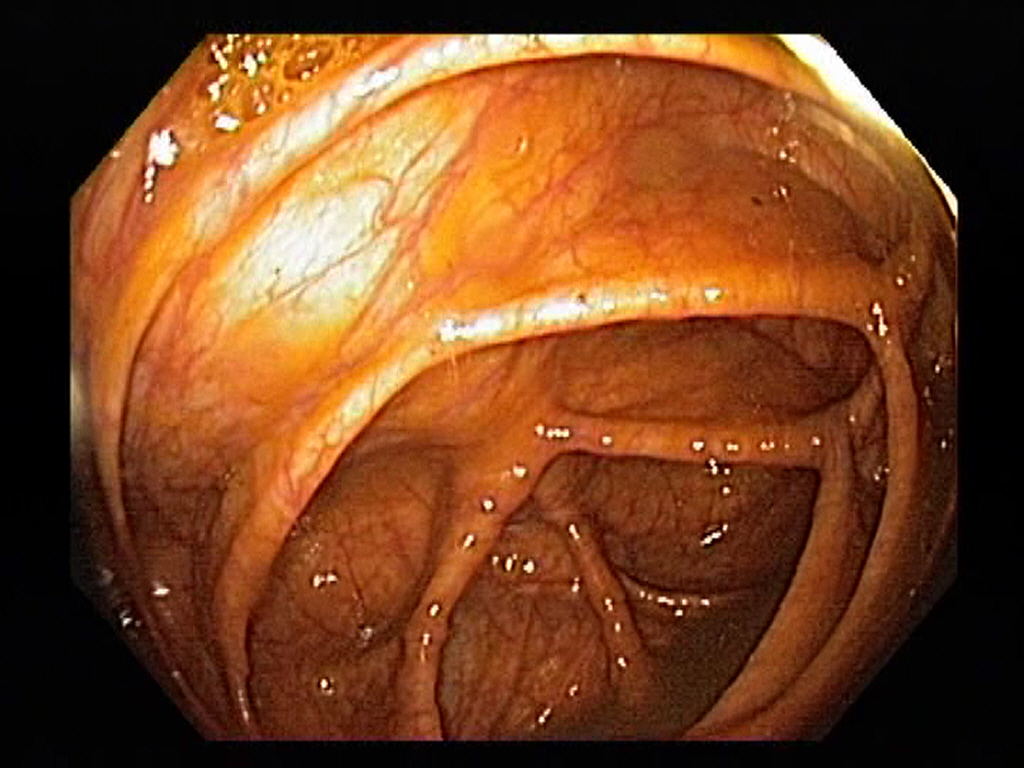

Normal Ascending Colon